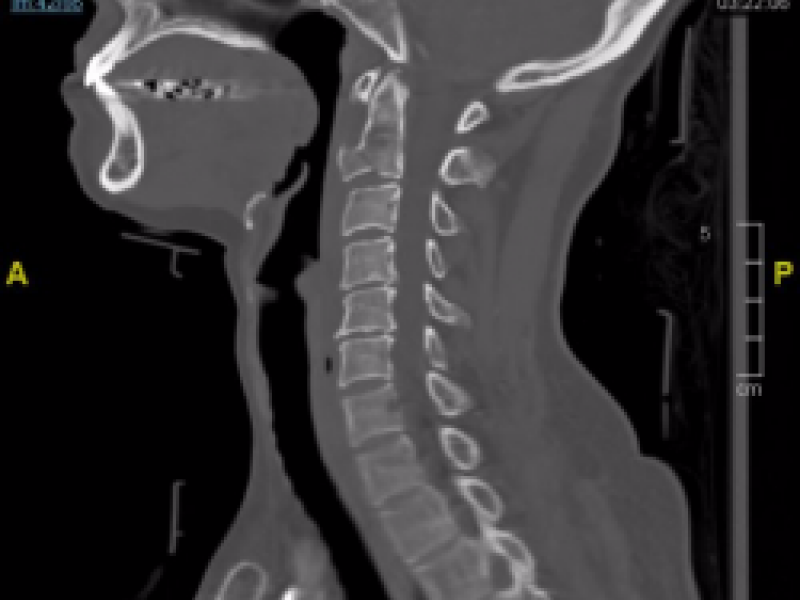

Back to Basics: Fracture Terminology

Using basic terminology, you should be able to describe any